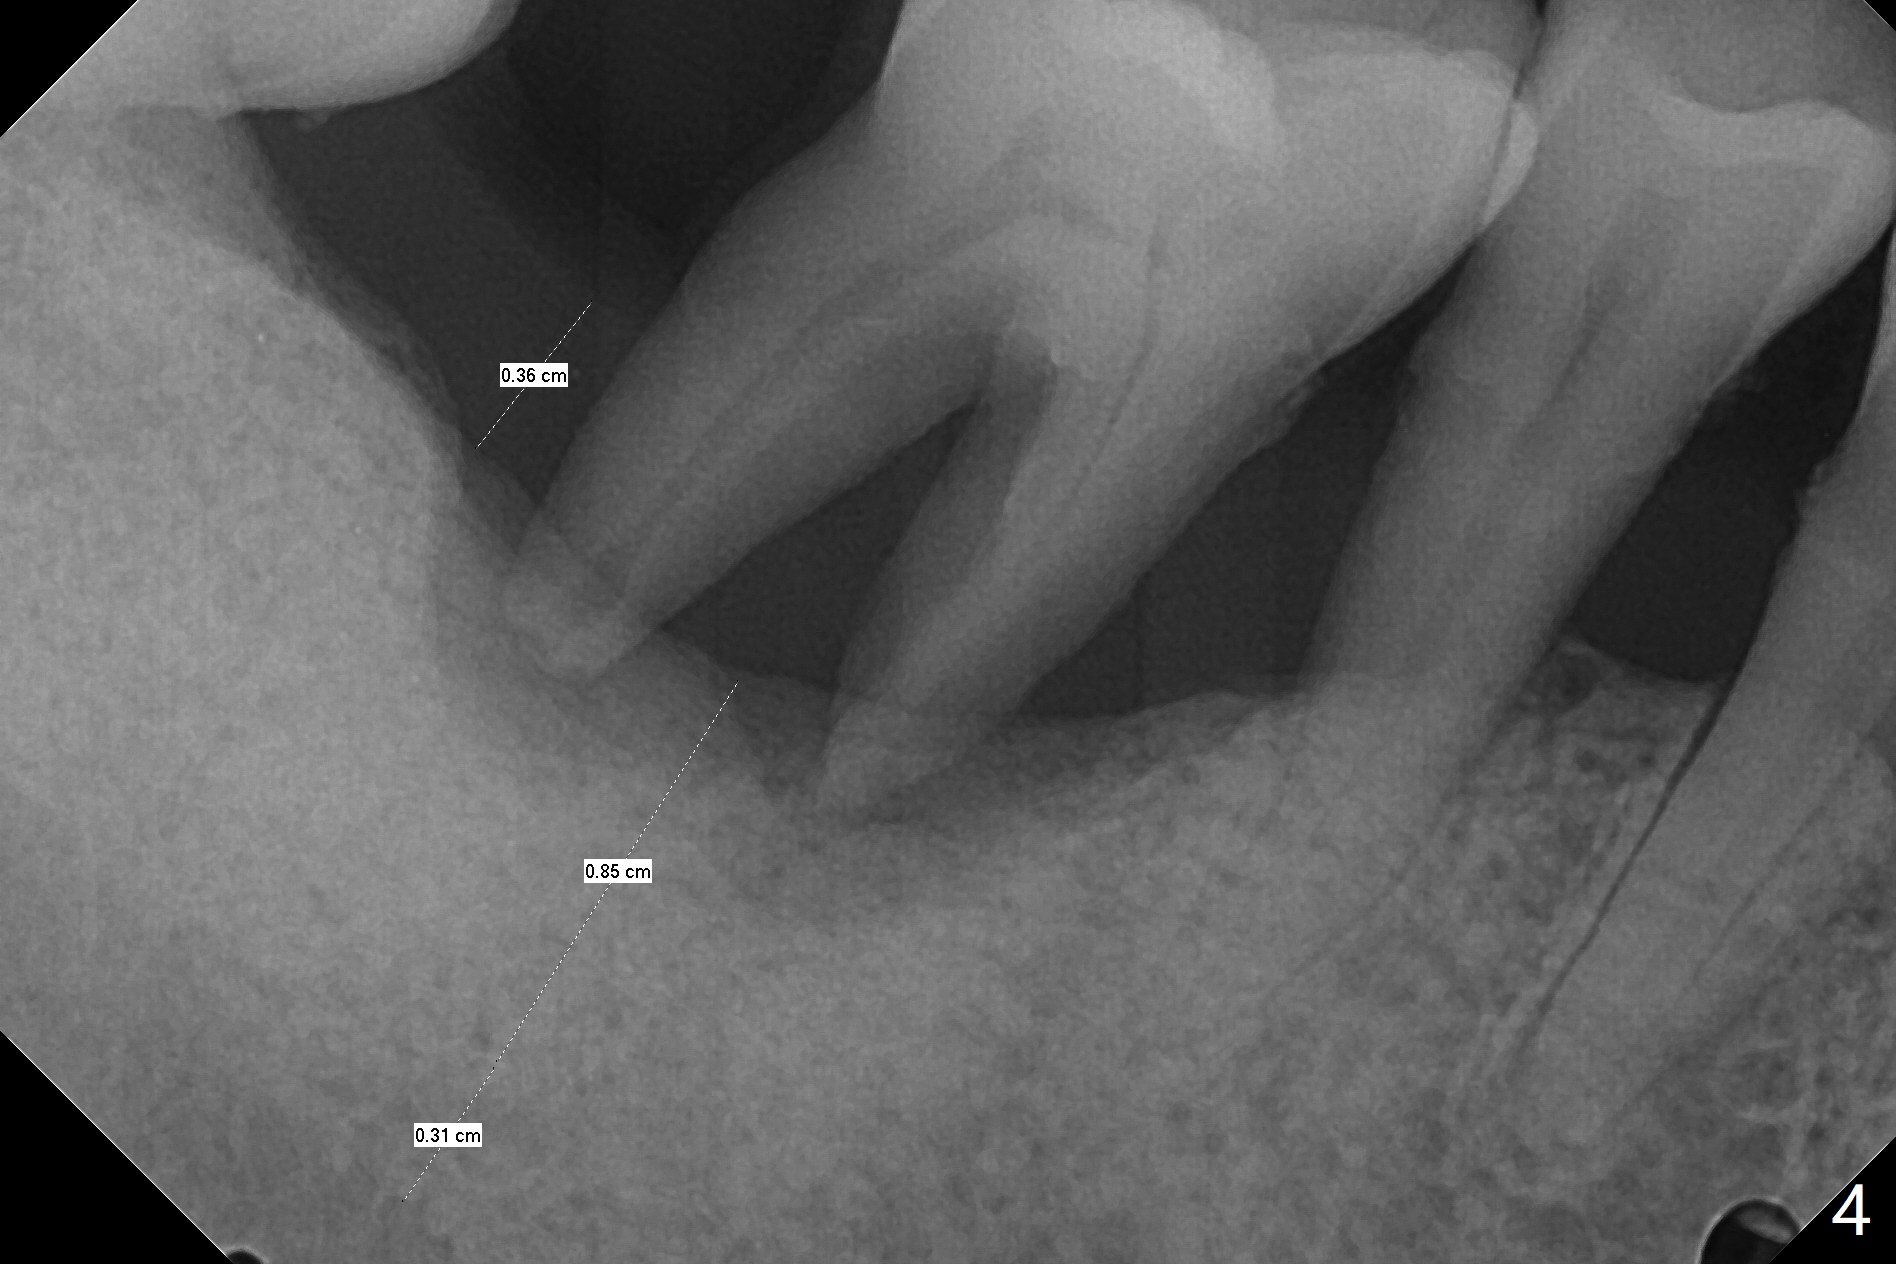

69岁男拔除左上5后右下6疼痛,要求拔除,骨质吸收严重,牙龈厚(图一:双箭头),其实后者是好事,血供好,植牙可以种植浅些(图二),周围放置骨粉(图三:红圆圈)。拍摄根尖片:近中牙槽窝种植与中隔种植,植体长度有优势(图五,四)。